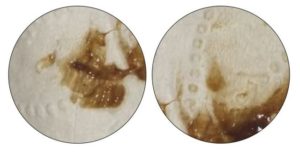

Подобная слизь вырабатывается в умеренном количестве и имеет такую консистенцию, что при попадании на ежедневную прокладку или белье, быстро растекается и впитывается, создавая эффект неравномерно размазанных пятен. Их фото вы можете увидеть ниже.